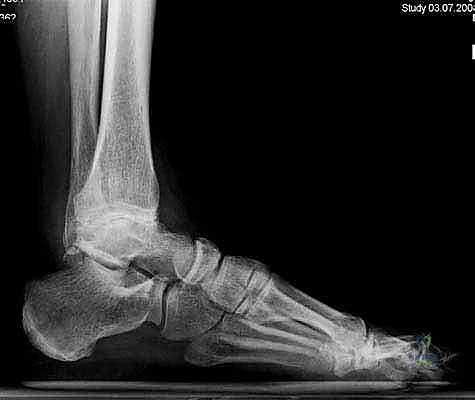

لفهم أهمية جراحة استبدال الكاحل، يجب أولاً فهم تشريح هذا المفصل المعقد. يتكون مفصل الكاحل من التقاء ثلاث عظام رئيسية:

1. عظمة الظنبوب (Tibia): وهي عظمة الساق الكبرى التي تشمل الجزء الداخلي والعلوي من الكاحل.

2. عظمة الشظية (Fibula): وهي عظمة الساق الصغرى التي تشكل الجزء الخارجي من الكاحل.

3. عظمة الكاحل (Talus): وهي العظمة السفلية التي ترتكز عليها عظام الساق وتعمل كمفصلة للحركة.

تُغطى نهايات هذه العظام بطبقة ناعمة ومرنة تسمى الغضروف المفصلي، والذي يعمل كوسادة لامتصاص الصدمات وتقليل الاحتكاك أثناء الحركة. عندما يتآكل هذا الغضروف، تبدأ العظام بالاحتكاك ببعضها البعض، مما يسبب ألماً مبرحاً وتورماً وتيبساً.

يتم إجراء فحوصات شاملة تشمل الأشعة السينية (X-rays)، والأشعة المقطعية (CT scan) لإنشاء نموذج ثلاثي الأبعاد لكاحل المريض. يساعد هذا د. هطيف في اختيار الحجم الدقيق للمفصل الصناعي وتحديد زوايا القطع بدقة متناهية.